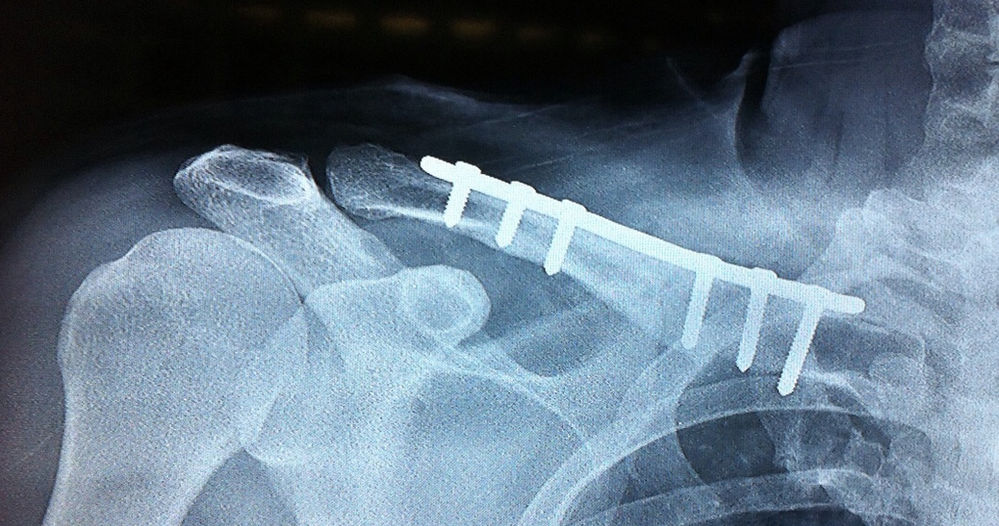

Tem Um Pino No Meu Ombro, Fiz Uma Cirurgia Para Acrômioclavilar, Esse Pino Vai Furar A Pele E Sair,. Boa tarde, fiz cirurgia de clavícula com enxerto ósseo, foi colocado uma uma aste de platina e 7 parafusos já faz 55 dias ainda sinto um pouco de dor no ombro na parte de trás, queria saber se já posso voltar a dirigir e pilotar moto.. Falamos de forma simples e direta para ajudar pacientes em assuntos de Ortopedia e Traumatologia.VOCÊ SABE COMO É A CIRURGIA E A RECUPERAÇÃO DA FRATURA DE CL.